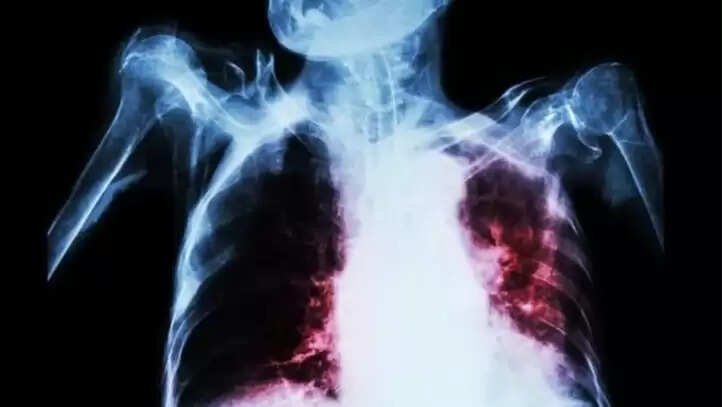

காசநோயால் கொத்து கொத்தாக செத்து மடியும் மக்கள்.. அதிர்ச்சி ஆய்வறிக்கை!

2015-ம் ஆண்டு இந்தியாவில் ஒரு லட்சத்துக்கு 237 காசநோய் பாதிப்பு இருந்தது, 2020-ல் ஒரு லட்சத்துக்கு 197 ஆகக் குறையும் என்றாலும், கடந்த 2-3 ஆண்டுகளாகத் தேக்க நிலை நீடித்து வருவதால் 2025-க்குள் காசநோயை ஒழிக்க முடியாது. கடந்த 2-3 ஆண்டுகளாக கட்டுப்பாட்டு திட்டங்கள் நடைமுறையில் இருந்தாலும். உலகில் காசநோயாளிகளில் நான்கில் ஒரு பங்கு இந்தியர்கள் பாதிப்படைகின்றனர். இந்தியாவில் மொத்தம் 25 லட்சம் பேர் பாதிக்கப்பட்டுள்ளனர். உலக அளவில் பாதிப்பு - 1.05 கோடி மக்கள். இந்தியாவில் ஒவ்வொரு ஆண்டும் 4,80,000 பேர் காசநோயால் இறக்கின்றனர். தினமும் 1,400 பேர் இறக்கின்றனர்.

காசநோயினால் ஏற்படும் பாதிப்புகள், இறப்புகள் மற்றும் வறுமையை நீக்குவதற்கான திட்டங்கள் இருந்தாலும், நோயைக் கண்டறிவதில் சிக்கல் உள்ளது. ஒவ்வொரு ஆண்டும் 10 லட்சம் பேருக்கு காசநோய் இருந்தாலும், இந்தியாவில் அது கண்டறியப்படாமல் உள்ளது (Missing TB). இந்தியாவில் உள்ள முக்கிய பிரச்சனைகள் என்னவென்றால், பெரும்பாலான காசநோயாளிகள் கண்டறியப்படாதவர்களாகவும், சிகிச்சை அளிக்கப்படாதவர்களாகவும் உள்ளனர்.